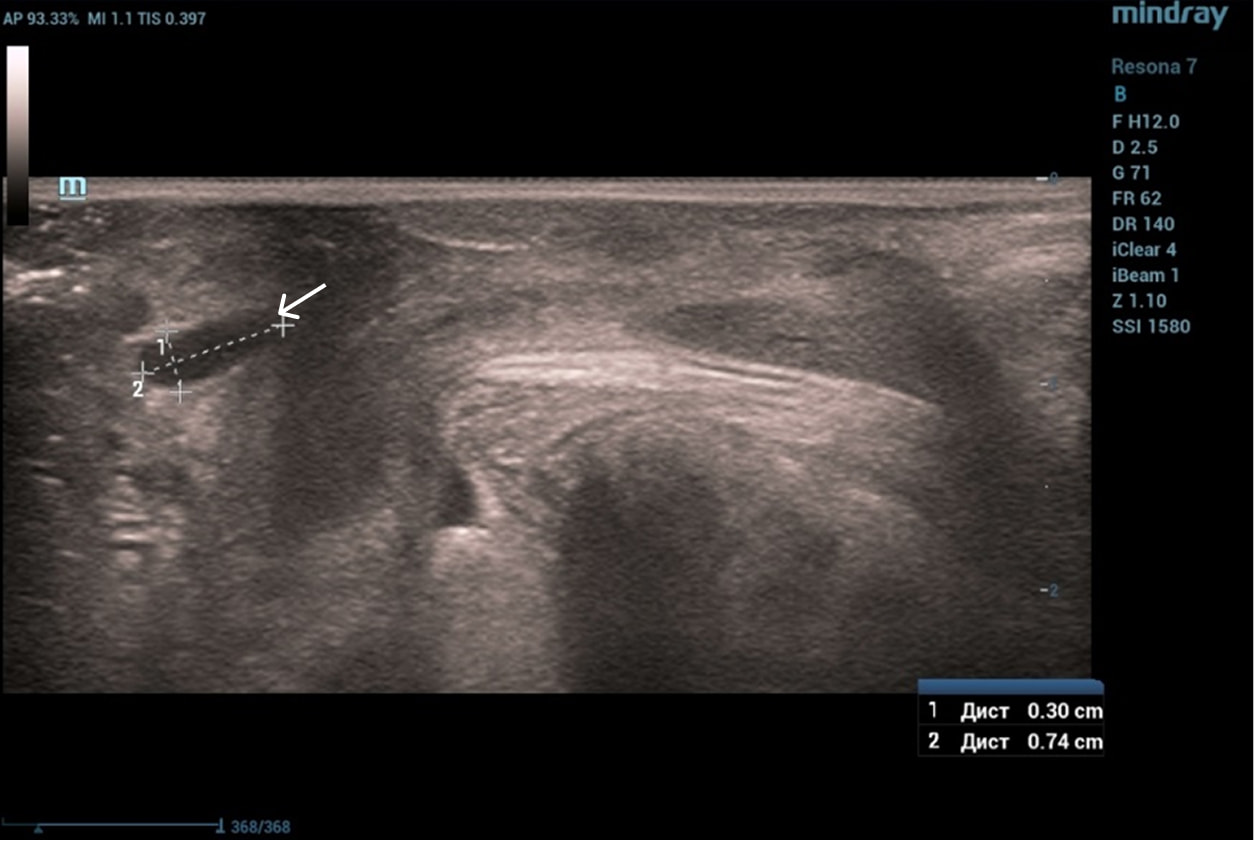

Эхограммы периуретральной области

Трансперинеальный доступ, линейный датчик.

Слева от уретры округлое образование с четкой капсулой и мелкодисперсной взвесью размерами 1,5×1,0 см (филлер с воспалением), справа — анэхогенное овоидное образование (филлер).